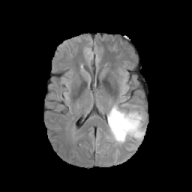

Brats MRI T1 Scans, FLAIR, Tumors. Lastly, we used a dataset of brain MRI scans [28] with two modalities: T1 (naive) and FLAIR (T2 Fluid Attenuated Inversion Recovery) [15]. We adapt the protocol that Cohen et al. [9] used for the Brats2013 datasets [27] to the more recent Brats2018 [3] dataset by varying the percentage of scans with tumors in the target domain. We selected transverse slices from the to range in the caudocranial direction [1] for both T1 and FLAIR scans. Each scan was classified as tumorous if more than of its pixels were labeled as such, and as healthy if it contained no tumor pixels. The training set contains images from each modality, with all source images (T1) being healthy and the target domain (FLAIR) comprising tumorous scans. The test set contains paired scans of healthy brains.

We adapt the protocol of Cohen et al. [9] from the Brats2013 datasets [27] to the more recent, larger, and more diverse Brats2018 dataset [2]. We consider two MRI modalities: native (T1) and Fluid Attenuated Inversion Recovery (FLAIR). We selected transverse slices from the to range in the caudocranial direction [1] for both modalities of scans.

We label each scan as tumorous if more than of its pixels are labelled as such, and as healthy if it contains no tumor pixels. We only use high-grade gliomas (HGG) instead of low-grade gliomas (LGG) as the are more easily observable [24]. In total, we obtain 5035 pathological pairs and 1135 healthy pairs. The train set is composed of a source domain of T1 images of healthy brains, while the target domain set is composed of FLAIR scans of which (60%) are tumorous and healthy. The test set is composed of aligned scans of healthy brains in both modalities.